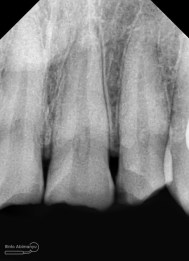

Begini kondisi klinis saat datang…

dan ini foto ronsen nya…

Dari pemeriksaan radiografis lokasi fraktur menyerempet kamar pulpa pada ketiga gigi tersebut… Saya sampaikan kepada pasien bahwa ketiga gigi tersebut memerlukan perawatan saluran akar terlebih dahulu baru kemudian dilanjutkan dengan restorasi indirek… kenapa saya pilih restorasi indirek? Pertimbangannya adalah sisa struktur mahkota gigi yang ada bila hanya di “sambung” dengan restorasi direk dalam jangka panjang rentan mengalami kerusakan, yang kedua pemilihan warna akan lebih maksimal pada kasus ini…. Pasien setuju dengan rencan perawatan yang saya jelaskan…